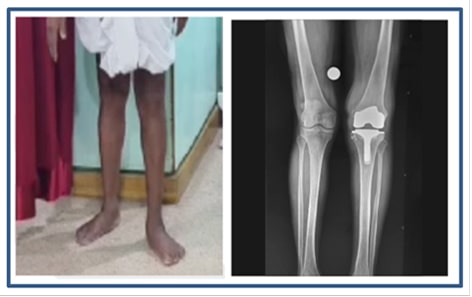

The knee deformity was completely corrected

Proper limb alignment was restored

No residual deformity remained after surgery

Implant positioning achieved optimal balance and stability

After Surgery